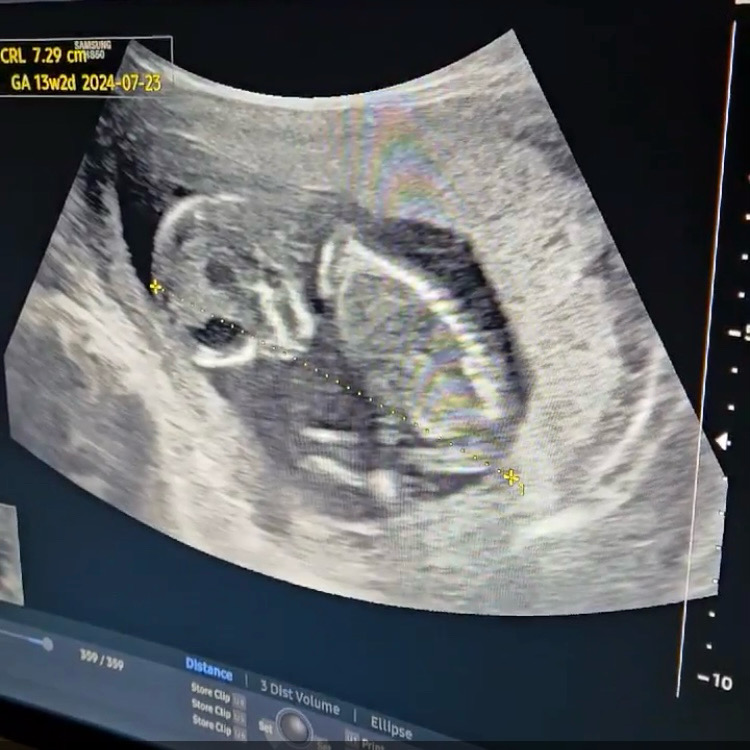

13주차 초음파🧡

오늘은 입덧약이 똑 떨어져서 호다닥 병원가서 처방받고 건강하게 잘 자라고 있는 애기 한번 더 보고왔어요 요로케 자고있는데 왜캐 귀엽죠..원장님이 아들같다는데 정확한건 2주뒤에 2차기형아 받을쯤 15주차에 알수있다 말하셨는데 반전이 있을까요 ㅎ